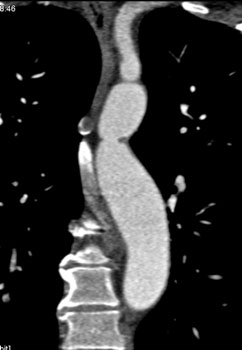

![]() | Question 19: Patient presents with right arm hypertension and normal to low pressure in the legs. What is the best diagnosis? |